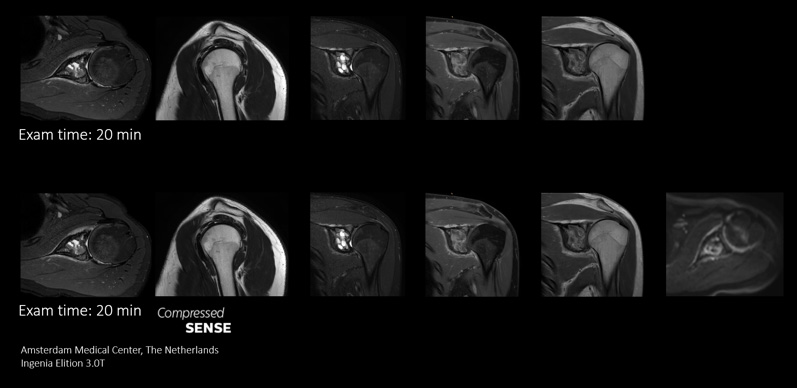

Higher spatial resolution, within the same scan time1

Rather than speeding up an MRI scan, Philips Compressed SENSE can be used to acquire images with higher resolution - in the same scan time currently allotted for an MRI exam - to increase diagnostic confidence. Sequences can be replaced or added to enhance critical details. A 2D sequence can be replaced with a 3D protocol to provide multiple orientations. Discover how compressed sensing applications can benefit the clinical areas you serve.

Enables up to 64% improvement in spatial resolution, within the same scan time1

Compare the image quality of an MRI scan performed with Compressed SENSE MRI software versus a conventional scanning technique

voxel size: 0.4 x 0.6 x 2.5mm voxel size: 0.3 x 0.3 x 2.5mm